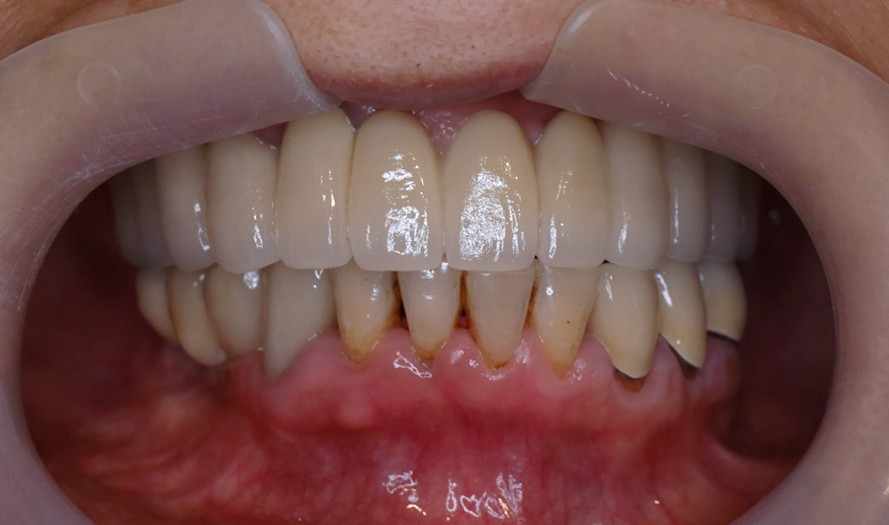

假牙完成